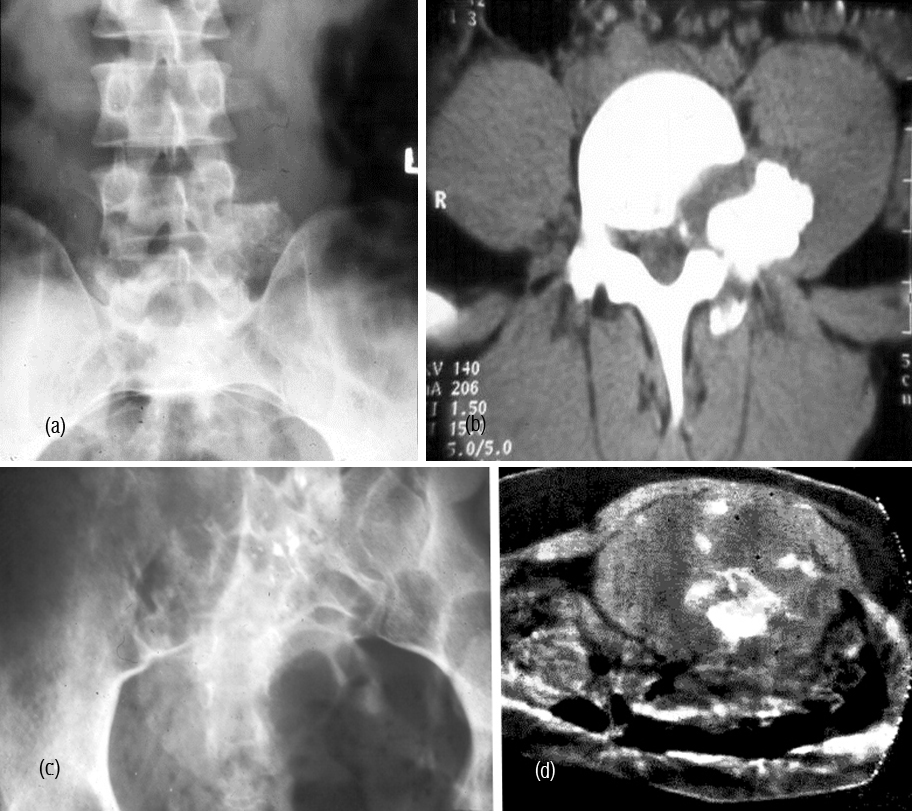

It is a solitary lesion and can be encountered in any bone. However, it is common in the spine. Most of the benign looking plasmacytomas when followed may develop into multiple myeloma eventually. Radiologically, a plasmacytoma is an expanding lytic lesion without any calcification or new bone formation. When it involves the vertebral body a compression fracture may be seen. When marked compression is seen vertebral plana is noted (Figure 1abc). To differentiate from metastasis, it is stated that in metastasis pedicles are involved earlier as they are vascular (2ab). However, when a large part of the body is involved in myeloma, pedicles also may be destroyed (Figure 3abc).

CT and MRI demonstrate lytic areas with struts of bone interspersed. In MRI, plasmacytoma shows a classical minibrain appearance (Figure 4abc). At times, it is difficult to differentiate hemangioma from plasmacytoma (Figure 5ab). It may remain localized for many years but more than 30% progress quite rapidly to generalized myelomatosis with a latent interval of 5-10 years. Radiological features are listed in table 1.

Figure 1a,b: Plasmacytoma with collapse of C3, T10. (c) Plasmacytoma – vertebra plana T8.

Figure 2: (a) Plasmacytoma of L2, (b) CT guided biopsy.

Figure 3abc: Plasmacytoma - Complete destruction of body of L3 including the posterior elements.

Figure 4a,b,c: CT - Plasmacytoma of sacrum, an expanding lytic lesion.

Figure 5: (a) CT (post op.), (b) MRI – Minibrain appearance